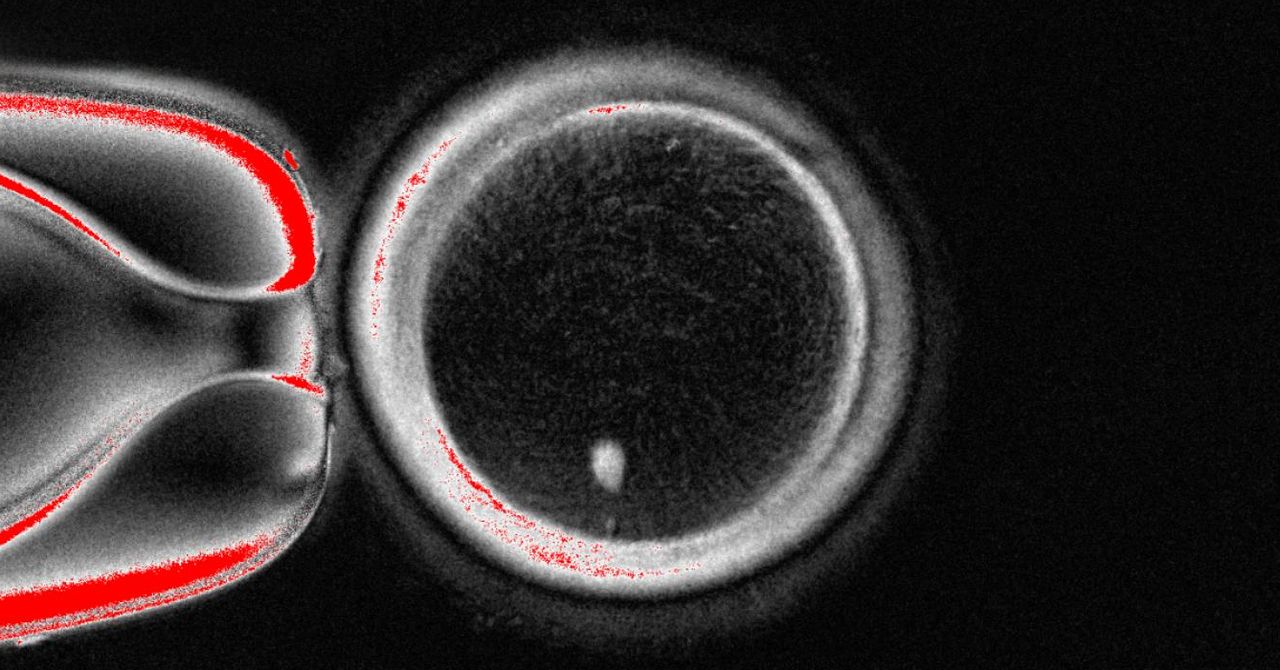

“The biggest challenge is how to make this egg transports half of the chromosomes – and the right half,” says Amato. “We are not there yet.” The team called “Mitomiosis” and tries to understand a better understanding of how to love chromosomes and how they are separated in order to find a way to experimentally urge these circumstances.

Metinori Saito at Kyoto University first documented in 2018 how his team Human blood cells have turned into stem cellsThen they turned into human eggs, but they were very immature so that they could not be fertilized to make embryos.

“Their method is very sophisticated and is well organized,” says Hayashi, a professor at the University of Osaka,. However, due to the high rate of chromosomal errors, “it is very ineffective and high risk to apply it immediately to the clinical application.”

Clark says: “The technique of artistic sclerosis is an important artistic innovation and can be of high value for our understanding of the biology of difference in human eggs. Selective errors increase with the progress of women. Therefore, understanding the causes of selective errors is a critical field of research.”